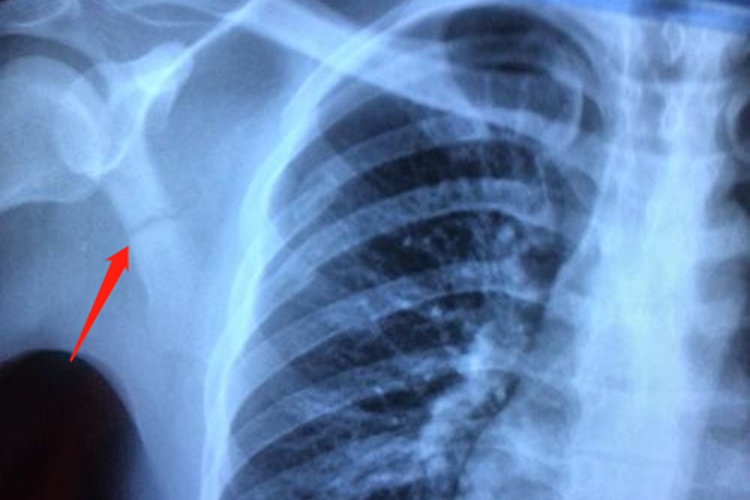

肩胛骨错位通常是由于外力作用导致,其治疗方法需根据错位程度和伴随损伤情况综合选择,如手法复位、冷热疗法等,但如果病情严重,也可能需要进行手术治疗。